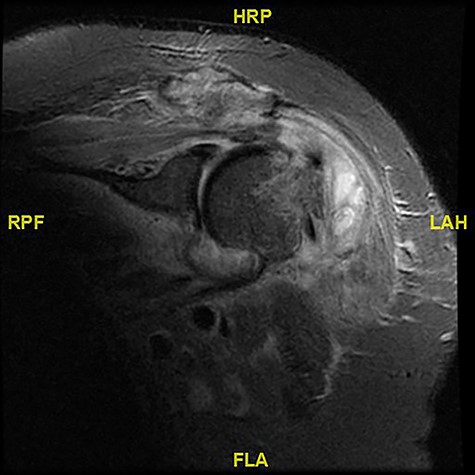

Magnetic resonance imaging (MRI) showed walled off loculations of pus around the proximal humerus with myositis and evidence of septic arthritis.